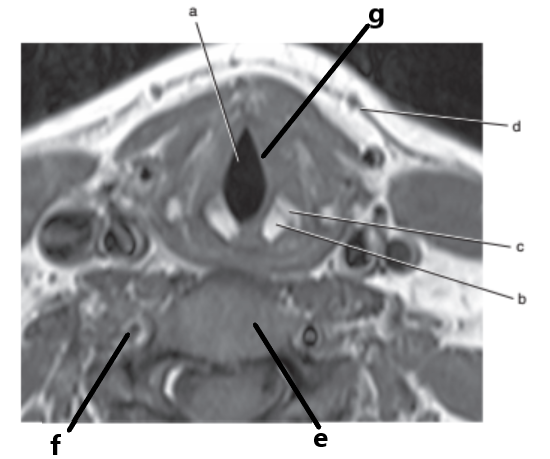

Epiglottis

Vocal cords

Glottis